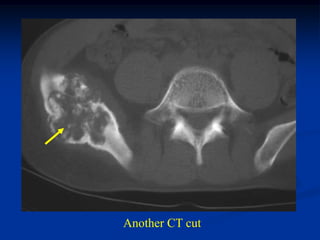

Case #595

46 year female with periosteal chondroma humerus

CT scan

Another CT cut

Coronal T-1 MRI

Coronal T-2 MRI

Photomic